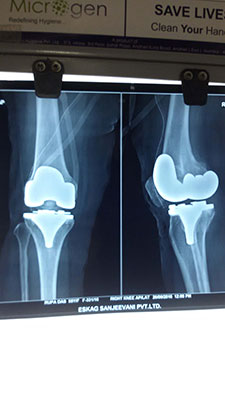

Case 9: Total Knee Replacement

Images

X-RAY 1

X-RAY both knees

X-RAY 2

X-RAY 3

X-RAY 4